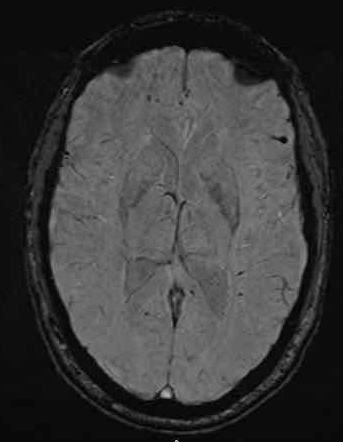

下图 一位46岁的男子骑摩托车时受伤。

瞳孔无反应性,瞳孔扩张。

CT:额叶点状出血。

继续做核磁共振成像

弥漫性轴索损伤(DAI)MRI表现

- 累及皮质下区、胼胝体、右侧丘脑和壳核、脑干、小脑脚和右侧小脑半球。

- 轻度全球萎缩。

MRI可准确诊断DAI,包括T2*GRE或SWI。

DAI在颅脑损伤患者MRI上的存在,更有可能导致不良的功能结局。